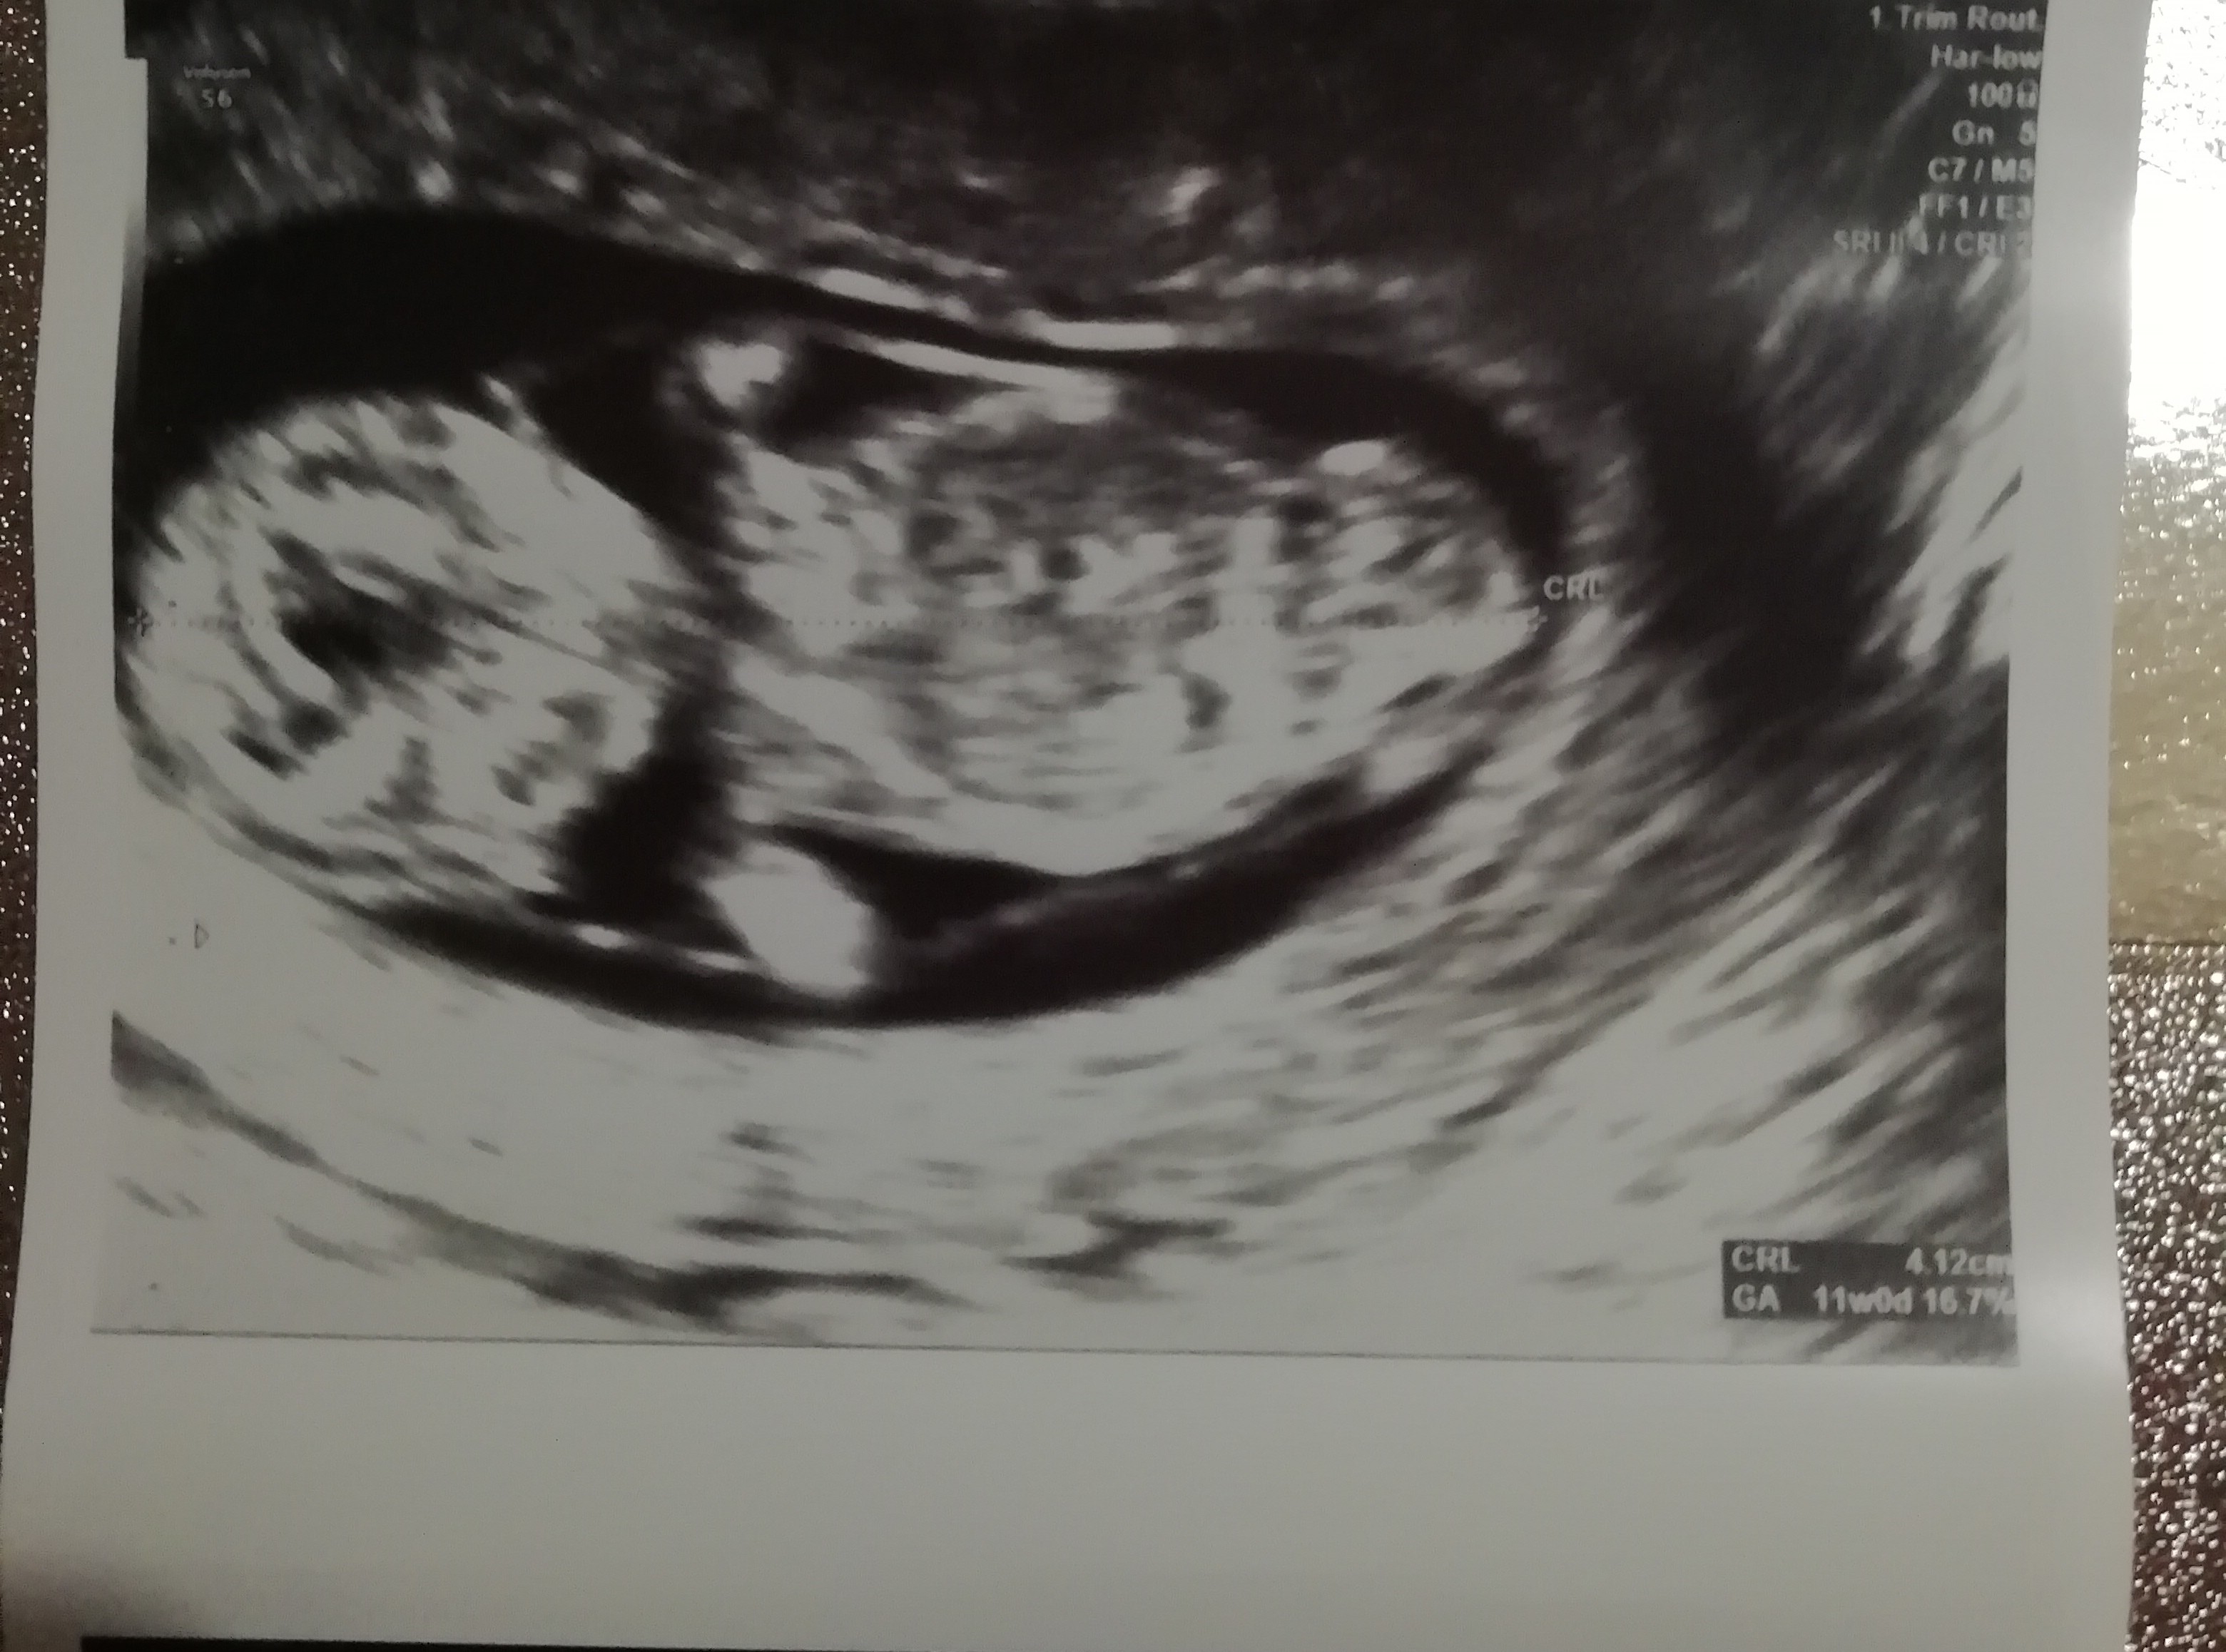

Nasze USG

27.02 :)

Tydzień ciąży : 11+1

CRL:4.12cm

Tętno :172/min

Oto mój uparty i leniwy skarb [emoji7] nie chciał się przekręcić i nie mogła pani wykonać NT ani NB , ale tak to wszystko z nim w porządku .Nadrobił tydzień i data porodu zmieniła się tylko o jeden dzień 17.09 na 18.09 . I najważniejsze krwiak się wchłonął [emoji2]